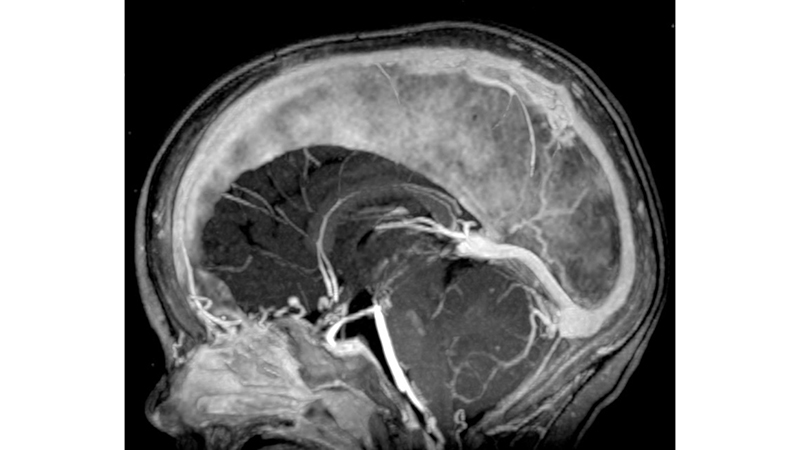

- Στην μαγνητική αγγειογραφία βλέπουμε υποσκληρίδιο αιμάτωμα στο δρέπανο

- και οπισθιοπλάγιους τροφοφόρους κλάδους από τις οπίσθιες εγκεφαλικές αρτηρίες.

- Τελική αγγειογραφία επανελέγχου του σπονδυλοβασικού μετά την δεύτερη συνεδρία εμβολισμού. Παραμένουν δύο με τρεις μικροί τροφοφόροι αρτηριακοί θαλαμοδιατιτραίνοντες κλάδοι από το Ρ1 τμήμα της αριστερής οπίσθιας εγκεφαλικής αρτηρίας, που λόγω του πολύ μικρού νεγέθους των θα αντιμετωπισθούν μετά από 2 έτη. Η φλεβική παροχέτευση γίνεται προς την φλέβα του Γαληνού, και διά μέσου επιπολής φλεβός προς την έσω επιφάνεια του αριστερού βρεγματικού λοβού προς τον άνω οβελιαίο κόλπο. Οι εγκάρσιοι κόλποι και ο Ληνός έχουν επανασηραγγοποιηθεί.

- Παρατηρείται πλήρης αποσυμφόρηση του περιμεσεγκεφαλικού φλεβικού δικτύου με σημαντική ελάττωση της φλεβικής συμφορήσεως περιμεσεγκεφαλικά καθώς και προς τον νωτιαίο μυελό.

- Πρόσφατη μαγνητική τομογραφία δείχνει αναστροφή των ισχαιμικών αλλοιώσεων του εγκεφαλικού στελέχους, αποκατάσταση του κοιλιακού συστήματος με ήπια υποεπενδυματική και φοιώδη ατροφία και πλήρη εξάλειψη των υποσκληριδίων συλλογών.